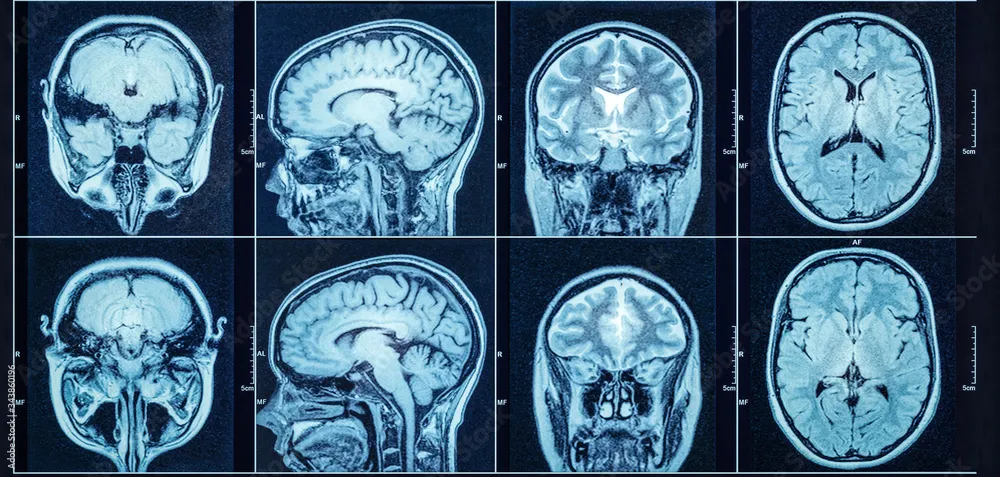

ADNI MRI Data Preprocessing for Absolute Beginner: A quick guide

ADNI dataset guide

Neural Network Architecture for the Classification of Alzheimer's Disease from Brain MRI

Custom model for detecting Alzheimer’s deceases